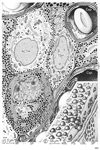

神経葉;神経部(下垂体の)Neural lobe of pituitary gland; Pars nervosa of pituitary gland(Lobus nervosus neurohypophysis; Pars nervosa neurohypophysis)

神経葉;神経部(下垂体の)【しんけいよう;しんけいぶ(かすいたいの)】 True posterior lobe of the pituitary gland.